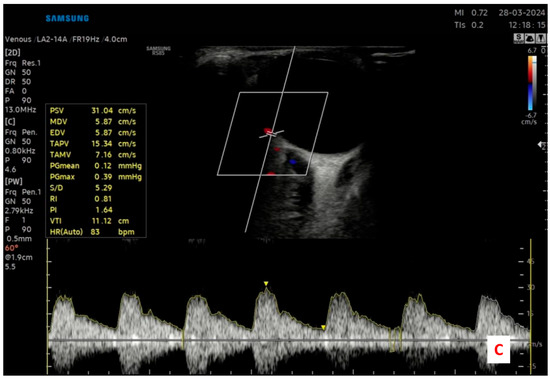

Measurements were taken from the ophthalmic artery (OA), central retinal artery (CRA), and posterior ciliary artery (PCA). For each vessel, the pulsatility index (PI) and resistive index (RI) were automatically calculated by the device’s built-in software, using waveform analysis. Care was taken to maintain the angle of insonation at ≤60° to optimize Doppler signal accuracy and avoid angular artifacts. The sample volume was adjusted to the vessel size, and the gate was placed in the center of the vessel lumen during measurement. Each measurement was obtained when a clear and stable Doppler waveform was visible, and three consecutive cardiac cycles were recorded for consistency (Figure 1).

Figure 1.

Representative color Doppler ultrasonography images demonstrating the retrobulbar blood flow assessment in a study participant. (A) Central retinal artery (CRA) identified within the optic nerve sheath; (B) Ophthalmic artery (OA) measured at the orbital apex; and (C) Posterior ciliary artery (PCA) evaluated near the optic nerve entry site.